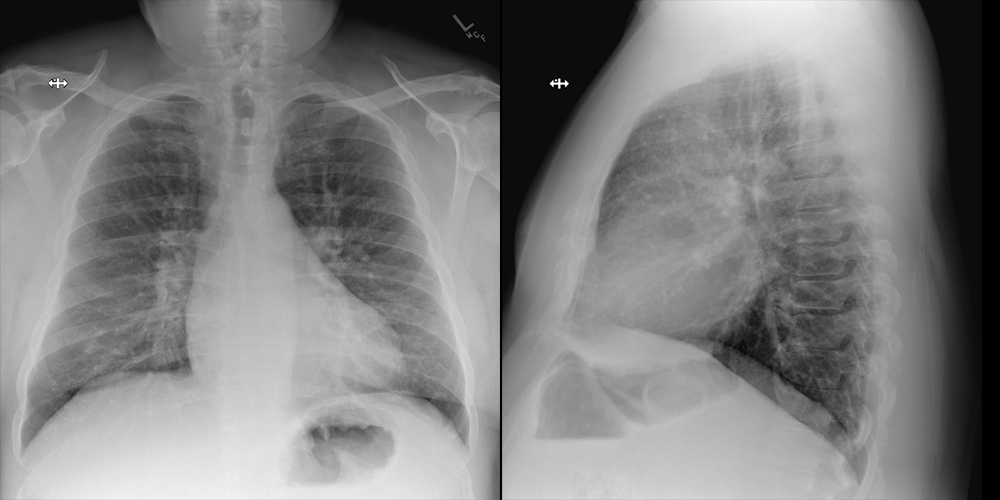

A chest X-ray may evaluate for an atypical pneumonia.

The clinical and imaging findings are most consistent with atypical (mycoplasma) pneumonia.

The patient is a young military recruit presenting with three weeks of worsening respiratory symptoms, low grade fever, and new onset anemia. Chest X-ray suggests an atypical pneumonia. The patient most likely has mycoplasma pneumonia. This can be definitively diagnosed with serology or PCR and treated with a macrolide antibiotic.